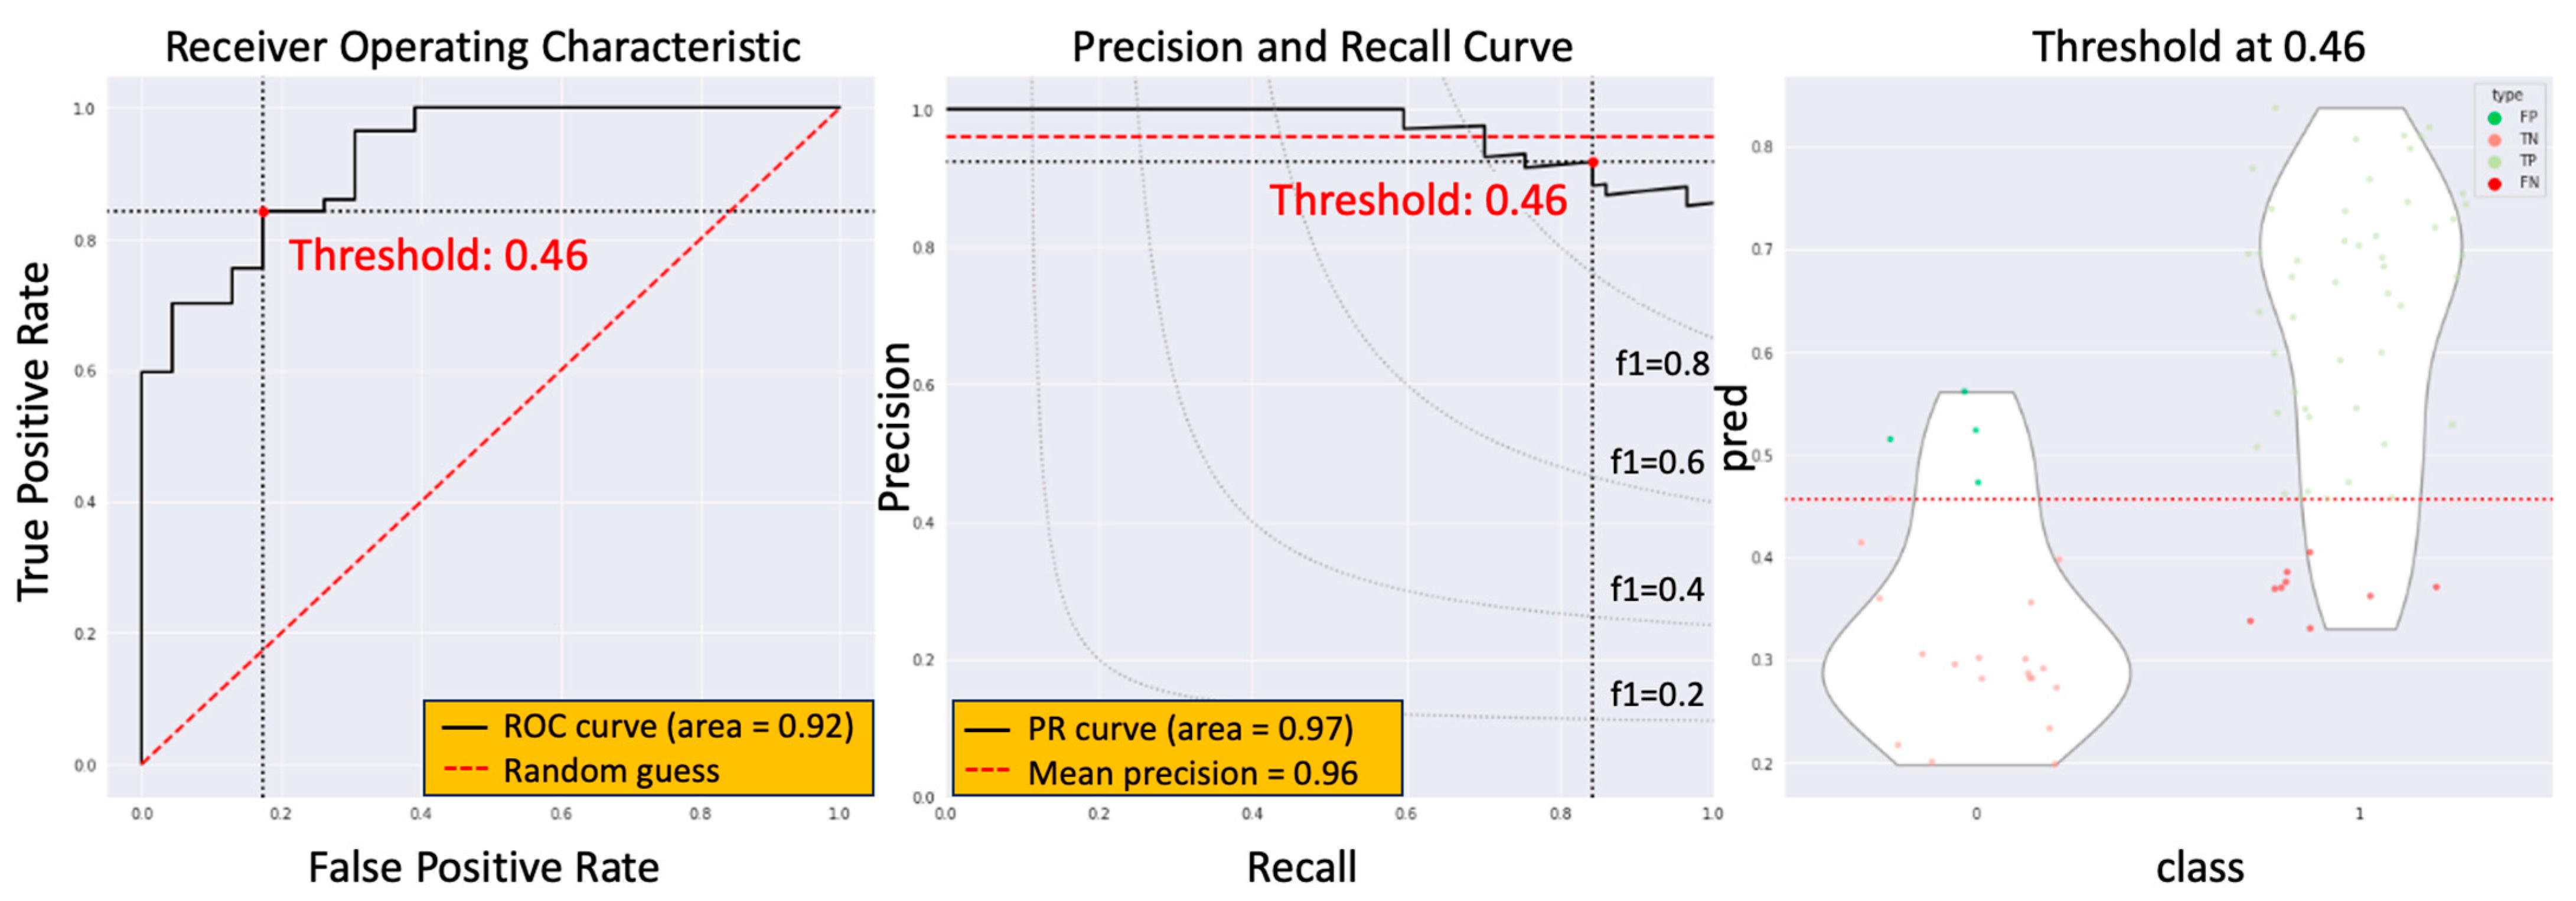

3.3. The Model Performance of DCRNet in Pathological Results